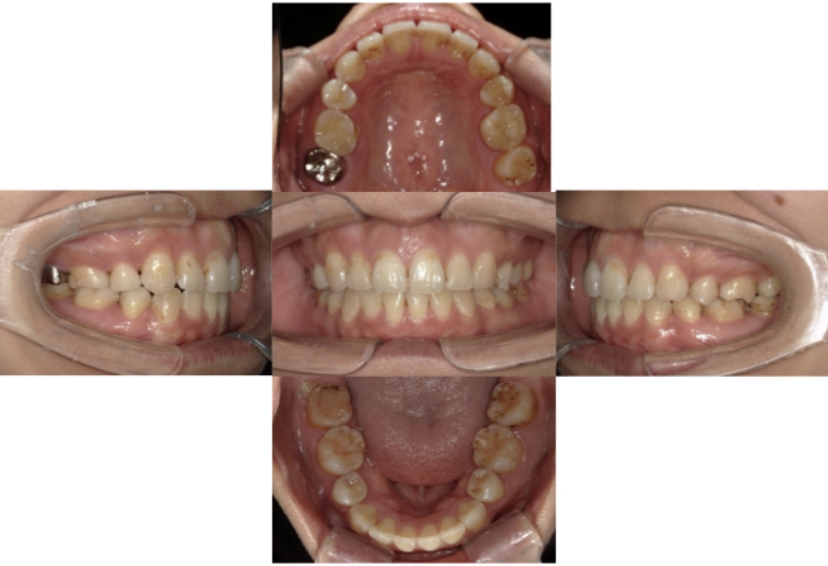

症例4

下顎前突、叢生

抜歯

ブラケット矯正

上下顎叢生、反対咬合(上下の前歯のガタガタ、若干受け口)のケースです。

装置はラビアル(上下表側)で、上下顎の小臼歯を4本抜歯を行っています。抜歯したスペースを使って、上下の叢生改善と前歯の受け口の改善を行っています。

主訴 前歯のガタガタを治したい。

年齢・性別 45歳 女性

お住まいの地域 神奈川県川崎市

治療方針 抜歯スペースを利用して上前歯の叢生(ガタガタ)の改善と受け口の改善

抜歯部位 上顎左右第一小臼歯、下顎左右第二小臼歯

使用装置 ラビアル(上下表側)、顎間ゴム

治療期間 2年6か月

治療回数 20回

リテーナー クリアリテーナー

BEFORE

AFTER